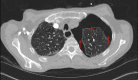

An Audaciously Aneurysmal Atrium